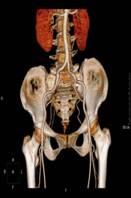

术前CTA检查